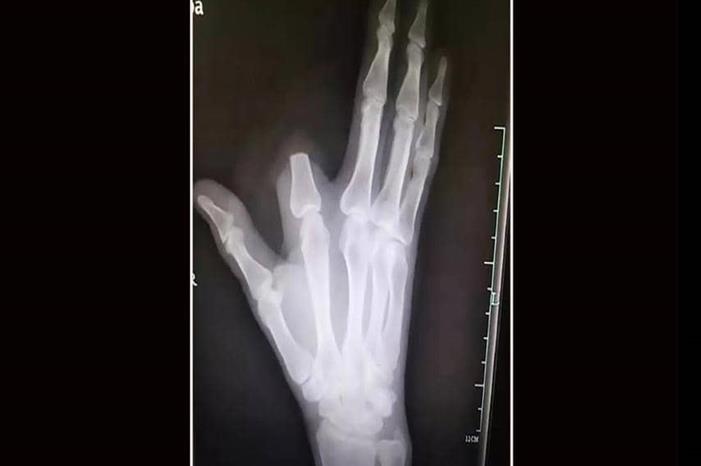

وظن الرجل أن لدغة الأفعى شديدة السمية وقد تؤدي إلى موته فورا، فسارع إلى قطع إصبعه بسكين كان بحوزته من أجل "إنقاذ حياته"، بحسب ما أوردت شبكة "فوكس نيوز".